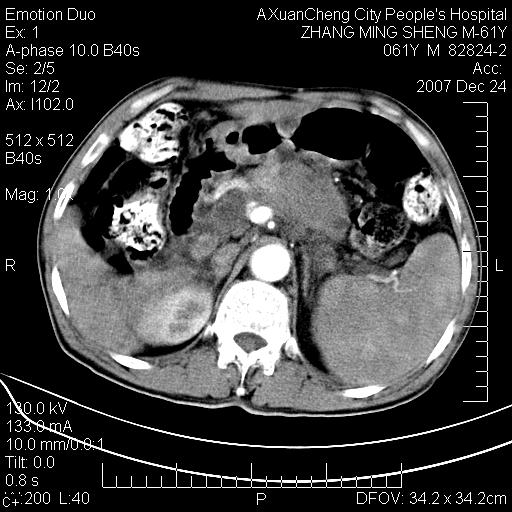

标题: CT11031:M61Y,胰腺占位

大家侃侃门静脉和胆管系统怎么回事,肝内转移?

胰腺癌肝转移

肝硬化,门脉高压,脾肿大;弥漫性肝癌,肝内、门脉、腹膜后淋巴结转移,肝内外胆管扩张,胰头区占位,建议mr检查

胰腺癌伴肝内转移;门脉、肠系膜上v癌栓形成。

考虑为:胰腺癌伴肝脏转移、腹膜后淋巴结转移,门静脉及肠系膜上静脉瘤栓形成。

胰体尾癌伴肝内转移,门静脉及肠系膜上静脉瘤栓形成.